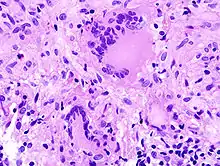

![]() Melanom-Metastase im Lymphknoten. |